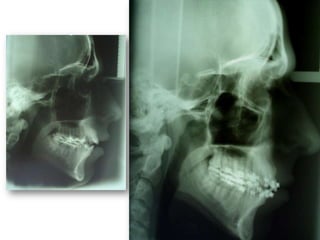

Atresia Maxilar Com Mordida Aberta

Atresia maxilarMordida aberta

anterior